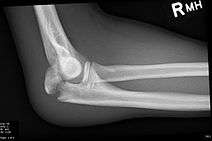

Olecranon fracture is a fracture of the bony portion of the elbow. The injury is fairly common and often occurs following a fall or direct trauma to the elbow. The olecranon is the proximal extremity of the ulna which is articulated with the humerus bone and constitutes a part of the elbow articulation. Its subcutaneous location makes it vulnerable to direct trauma. Powerful pull of the triceps muscle can also cause avulsion fractures.

Frontal and lateral X-ray views of the elbow are typically done to investigate the possibility of an olecranon fracture. A standard lateral view of the elbow insufficient to diagnose olecranon fractures. A true lateral x-ray is essential to determine the fracture pattern, degree of displacement, comminution, and the degree of articular involvement.